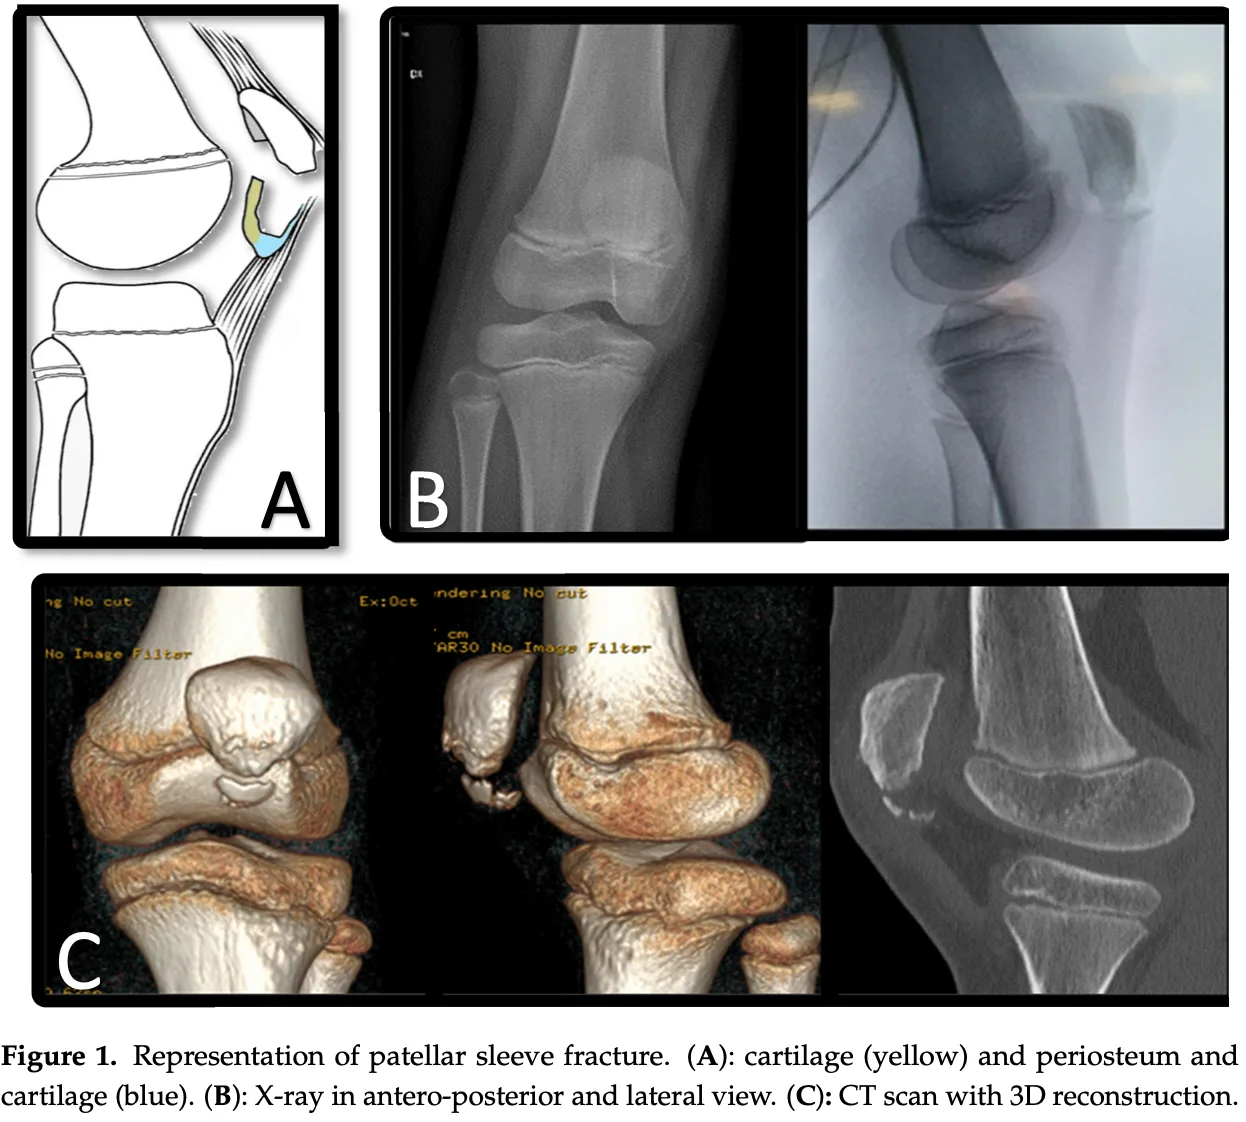

膝蓋骨下極が膝蓋腱に引っ張られることによって, 膝蓋骨本体から軟骨と骨膜が小さな骨片を伴って引き剥がされるように折れる骨折(剥離骨折)です.

引用元:Papotto G. Patellar sleeve fracture: An update of literature. Surgeries 2024. 5.

Sleeve骨折は, 膝蓋骨に付着する腱に引っ張られて, 膝蓋骨の一部(骨・骨膜・軟骨)が剥がれるように生じる骨折です. 小児の膝蓋骨に見られる剥離骨折の一種です.

ちなみに“sleeve”とは衣服の袖ではなく, レコード盤を包むジャケットカバーのこと.

膝蓋骨がレコード本体, そこから剥離した骨・軟骨・骨膜がsleeveに相当します.